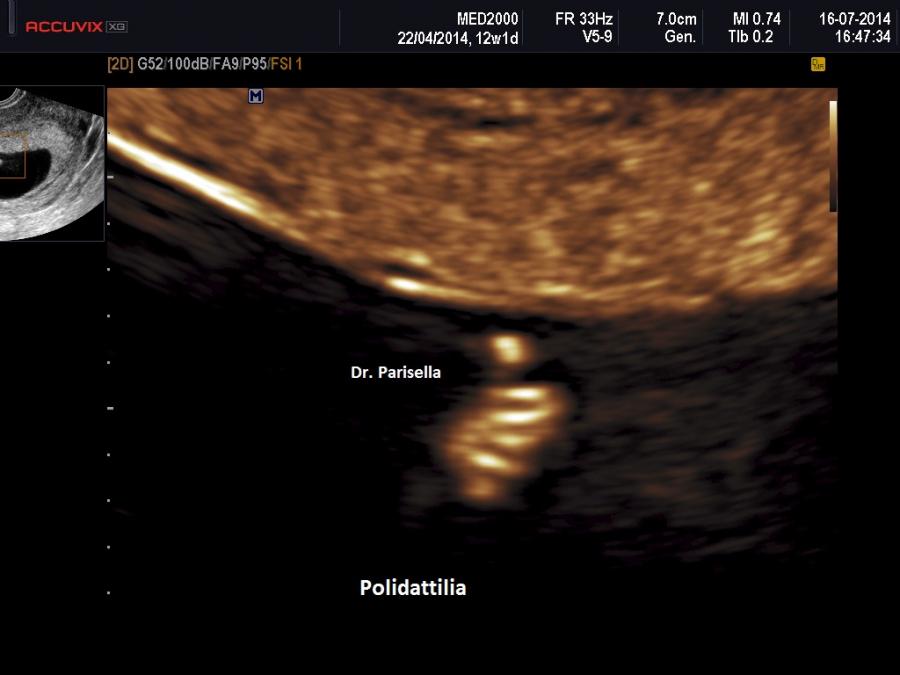

polidattilia

anomalie arti (fusione radio ulna, polidattilia )

L) anomalie arti (Limbs): aplasia radio, fusione radio ulna, polidattilia